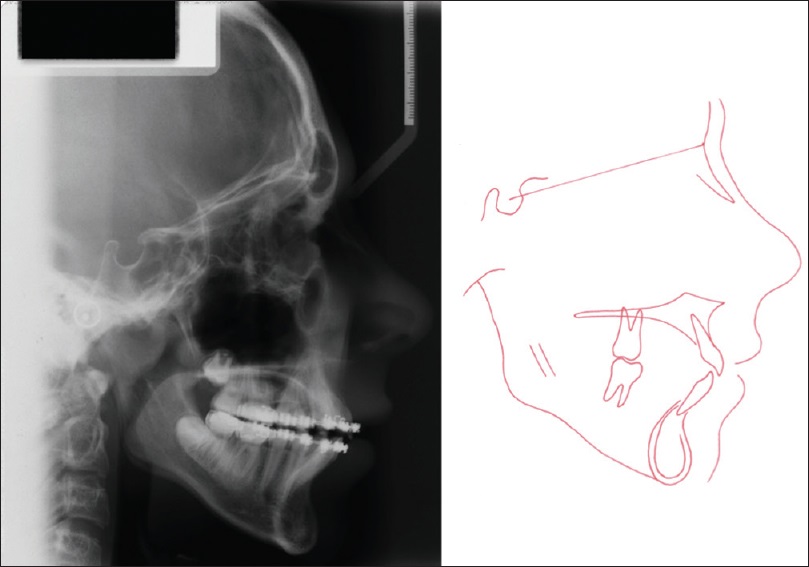

Figure 9. Posttreatment cephalometric radiograph and tracing